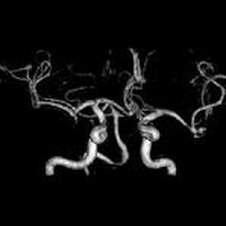

脳の病気で1番怖いものの1つに『くも膜下出血』があります.これは脳の血管にできた『こぶ』が破裂して起こる病気で約半数が命を落とします.脳ドックでは,MRIを用いて未然にこの『こぶ』を発見したり,脳梗塞の前兆や初期の脳腫瘍を発見することを目的としているほか,血液検査,心電図により脳卒中の危険因子をチェックすることを目的としています.当院では日本脳ドック学会のガイドラインに準拠した検査を行っています.現在1ヶ月あたり50-100件の検査実績がございます.万が一異常が発見された場合はご相談の上,適切かつご希望の病院にご紹介いたします.

7,MRI検査(頭部の断層撮影,頭部と頚部の血管撮影)